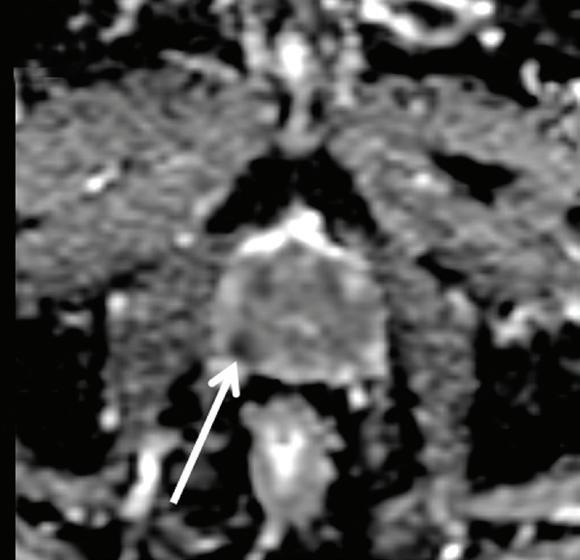

above: A 63-year-old man with right-side prostate cancer (shown by arrows) detected on 3T MRI of the prostate. Image D shows curves for average and worse pixels in the tumor. All images provided by Mount Sinai’s Department of Radiology and Translational and Molecular Imaging Institute.